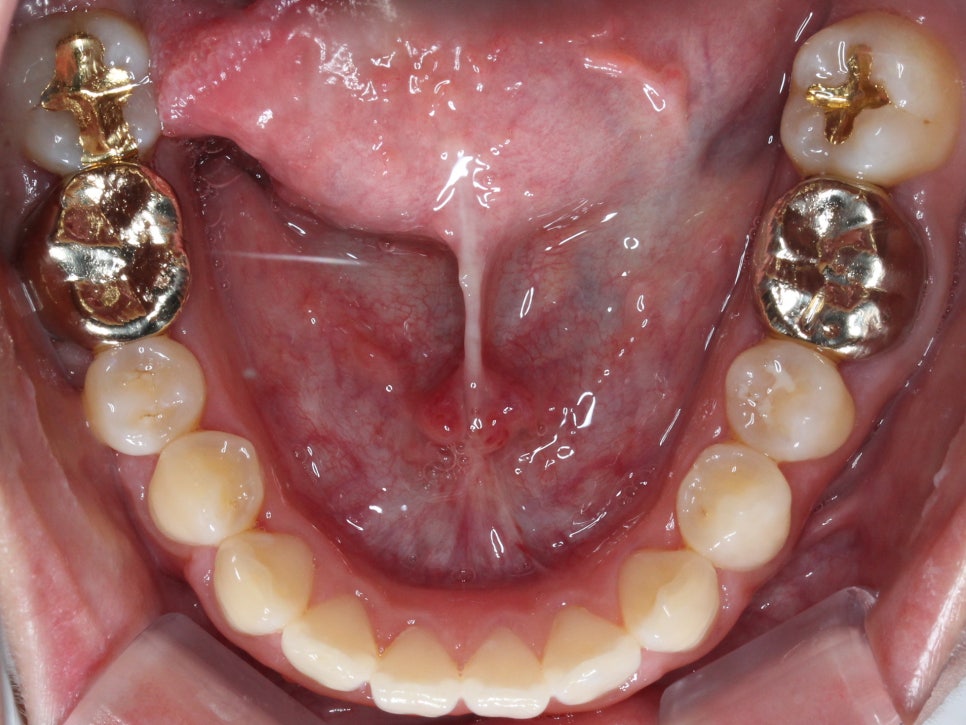

마무리 한 모습입니다.

브라켓을 붙이고 진행한 것은 아니라

디테일하게 중심선을 맞추거나

구치부 교합까지 완벽히 잡진 못하지만

환자분께서 원하시던

#12가 들어가 있던 모습과

뻗쳐보이는 느낌을 개선 후 마무리를 했습니다.

이렇게 투명교정을 통해

골격적 비대칭을 완벽히 해소하진 못해도

가지고 있는 골격 안에서

최대한 환자분의 니즈에 맞춰

교정을 할 수 있습니다.